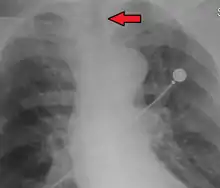

Ideally, at least one of the methods utilized for confirming tracheal tube placement will be a measuring instrument. Waveform capnography has emerged as the gold standard for the confirmation of tube placement within the trachea. Other methods relying on instruments include the use of a colorimetric end-tidal carbon dioxide detector, a self-inflating esophageal bulb, or an esophageal detection device.[36] The distal tip of a properly positioned tracheal tube will be located in the mid-trachea, roughly 2 cm (1 in) above the bifurcation of the carina; this can be confirmed by chest x-ray. If it is inserted too far into the trachea (beyond the carina), the tip of the tracheal tube is likely to be within the right main bronchus—a situation often referred to as a "right mainstem intubation". In this situation, the left lung may be unable to participate in ventilation, which can lead to decreased oxygen content due to ventilation/perfusion mismatch.[37]